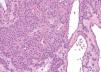

Las malformaciones venosas están constituidas por vasos ectásicos de tamaño variable, que asientan en la dermis profunda y tejido celular subcutáneo. Algunos son de pared fina, mientras que otros presentan una capa muscular gruesa. Es frecuente la presencia de trombosis y flebolitos, así como el hallazgo de áreas de hemorragia con depósitos de hemosiderina y calcificaciones extravasculares (fig. 10).

Figura 10. Vasos ectásicos de pared fina en dermis profunda correspondientes a malformación venosa. Hematoxilina-eosina, x100.